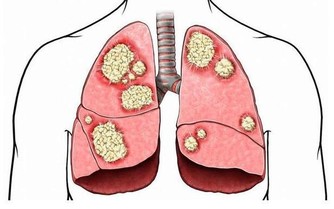

在我國慢性腎小球腎炎是導致慢性腎病的主要原因,而引發慢性腎小球腎炎的“源頭”則是反复的呼吸道感染,或者腸道等部位的感染。例如常見的咽喉炎、牙齦炎、尿路感染等。

這些因細菌或病毒導致的炎症感染複合物,經血液匯集到腎臟後,人體的免疫系統將它為“敵人”,於是對其進行清除,在清除它的同時損害了腎臟。此外,感染某種病毒還能改變腎小球濾過膜的性質,人體的免疫系統就把這種改變性質的組織當成了“壞人”然後消滅它,導致腎小球基底膜因此受傷。